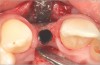

Fig 4. Implant inserted into the ridge, buccal view. There was a large labial concavity. The implant is seen on the buccal and terminates within the alveolar bone.

Figure 4